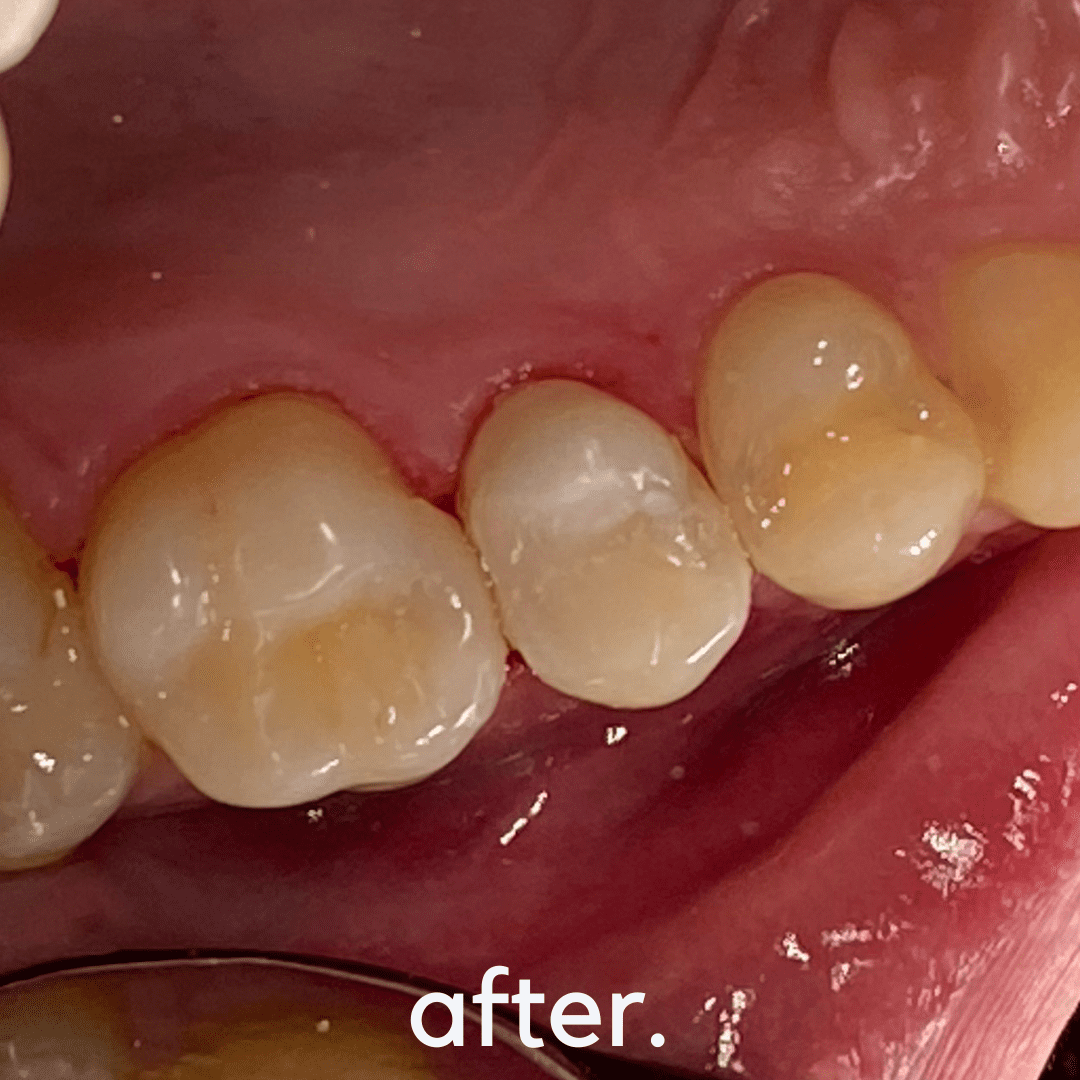

A root canal treatment is a minimally invasive procedure designed to remove infected or inflamed dental pulp, disinfect the root canal, and seal it with a biocompatible filling. This treatment eliminates pain while preserving your natural tooth structure, preventing the need for extraction and maintaining oral health and function.

✔ Restores Chewing & Speaking Function – Keeps your bite and speech natural

✔ Prepares for a Long-Lasting Restoration – A dental crown can further strengthen the tooth

🦷 Phase 3: Final Restoration – Dental crown or filling placement for durability